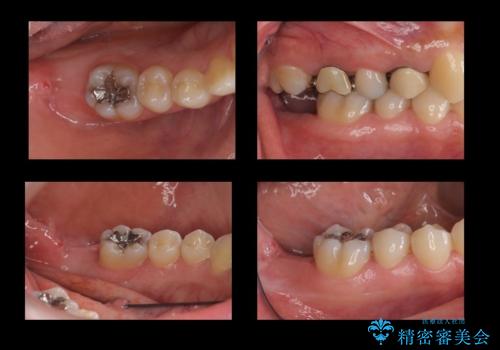

- 奥歯の虫歯を放置してしまい、痛みがあり来院。

下の奥歯が虫歯になっており、痛みが生じていました。

左右の第二大臼歯は虫歯がひどく抜歯が必要な状態でした。

また、左下の第一大臼歯は歯が内側から吸収してしまう状態(外部吸収)が生じており、患者様と相談の上抜歯しました。